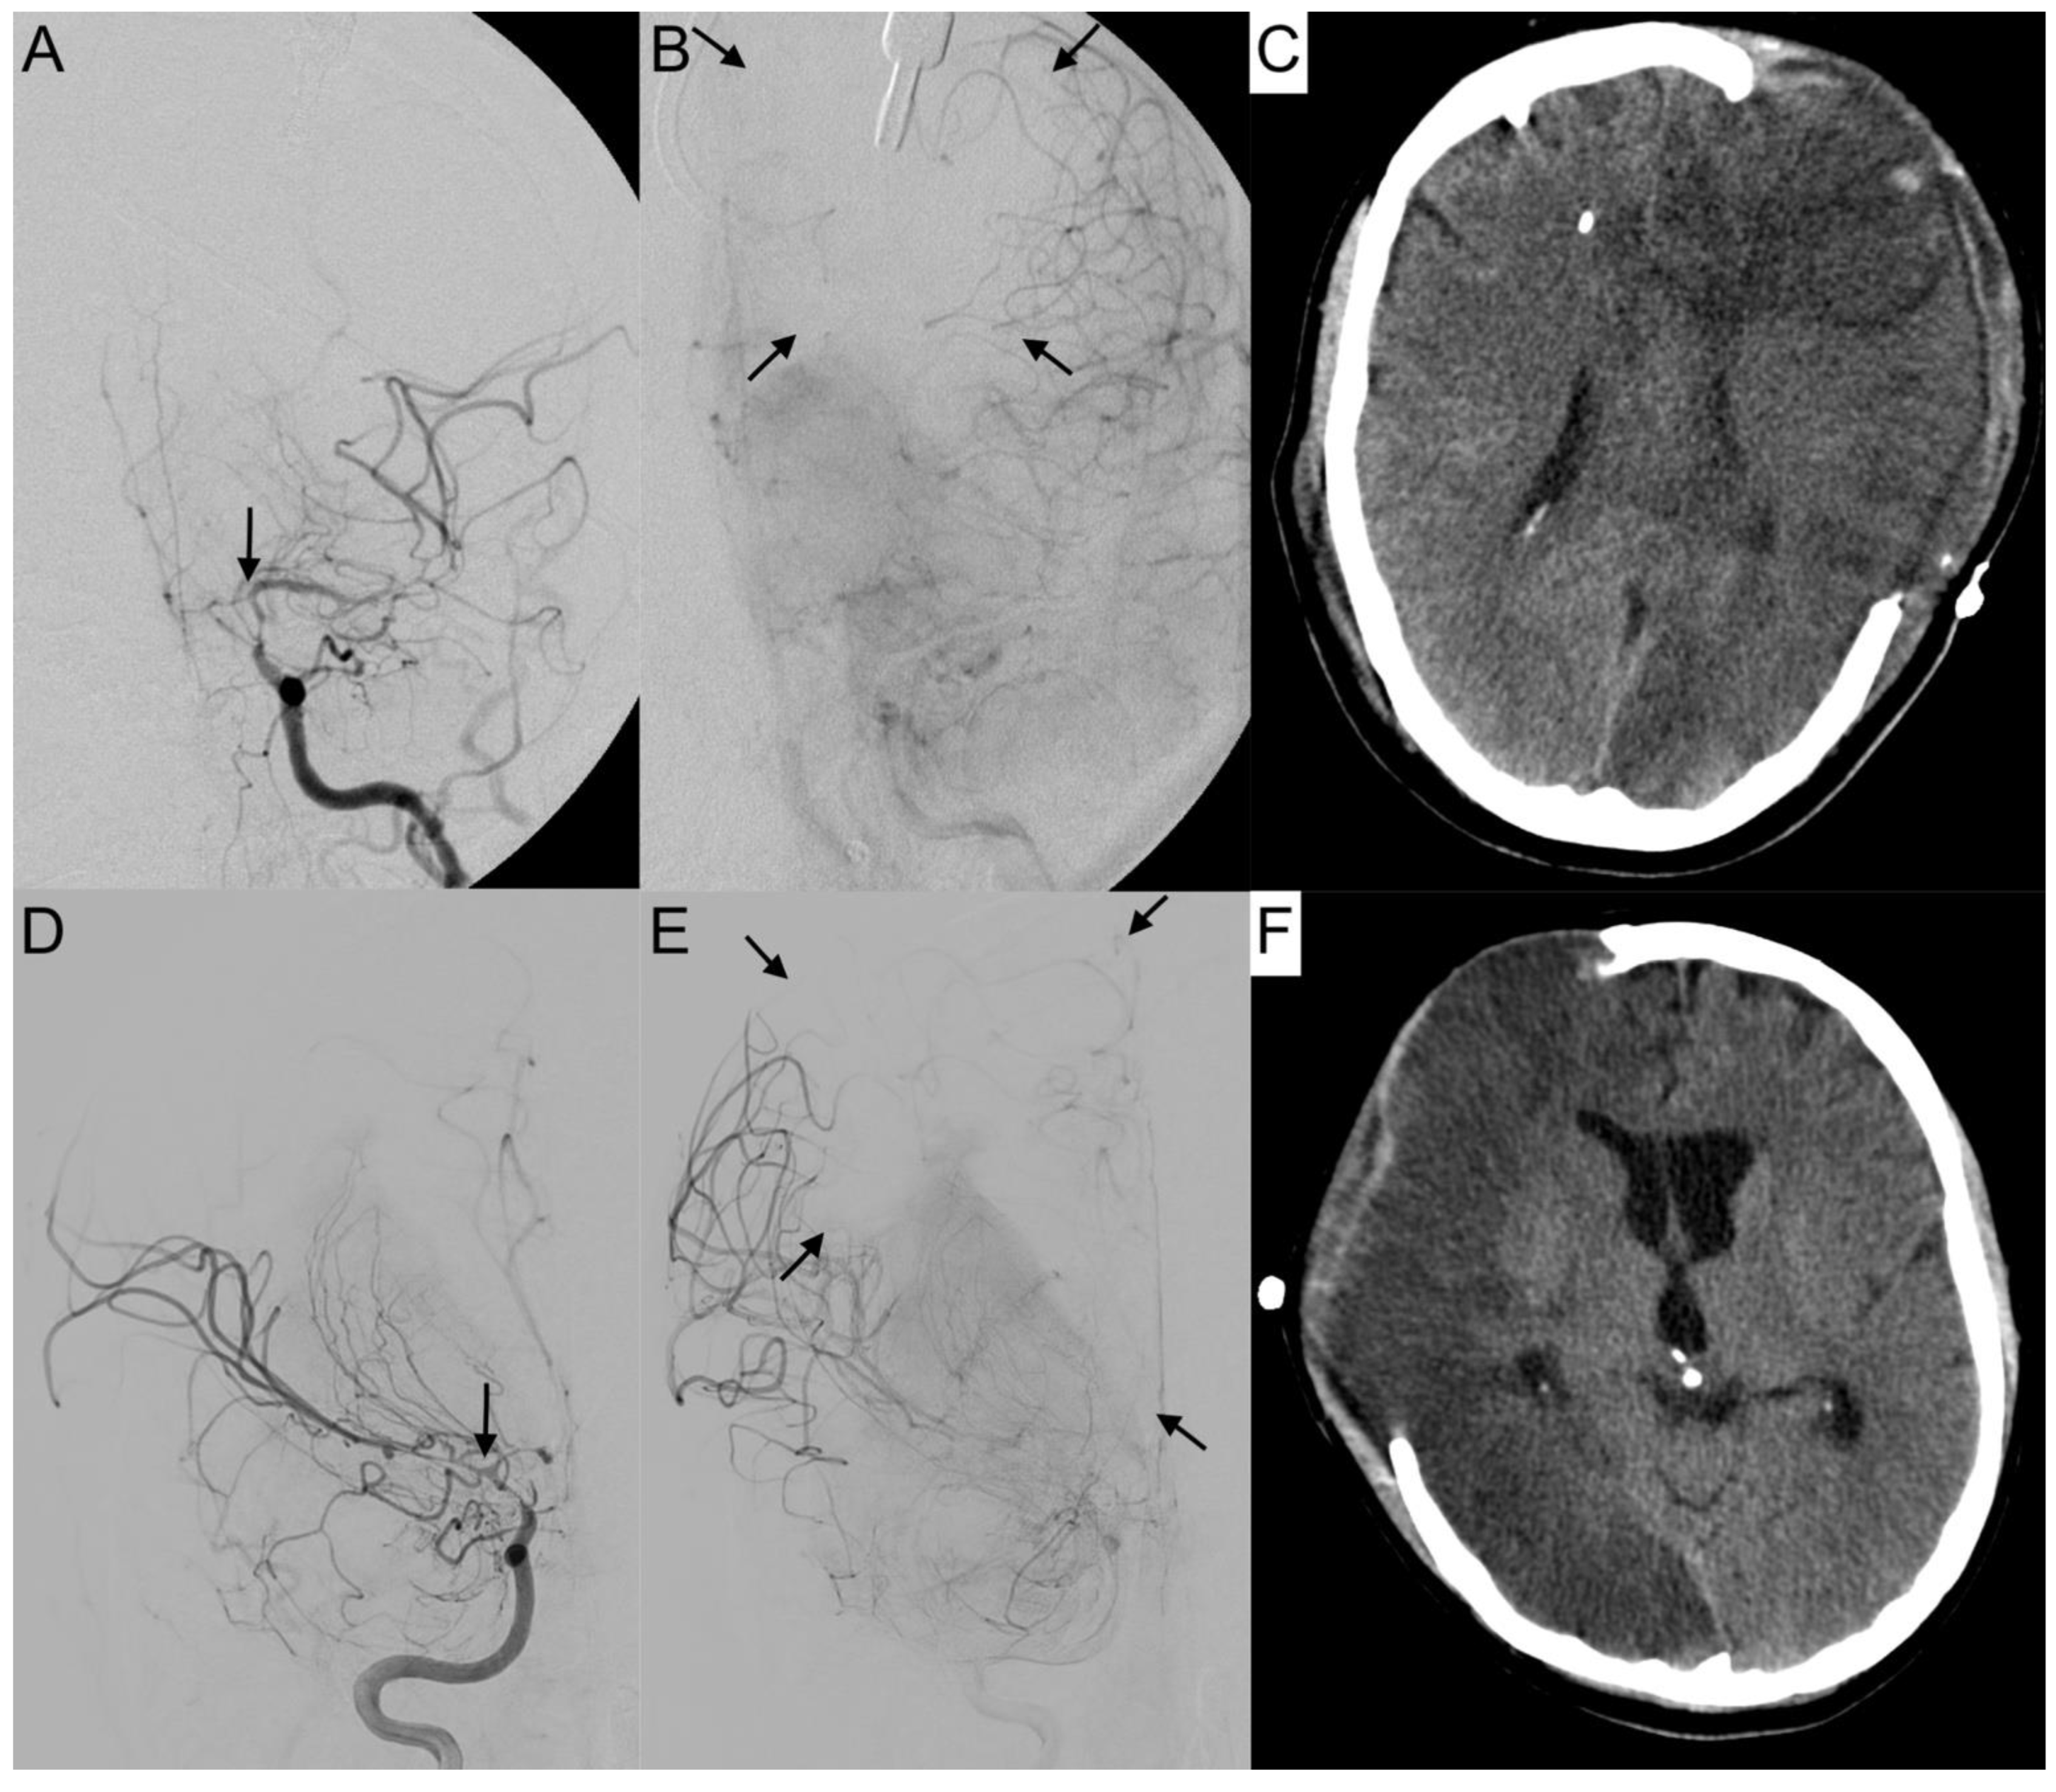

Figure 6. Collapsed collateral supply in severe vasospasm. Angiograms of the left (A,B) and right (D,E) internal carotid arteries (ICA) with severe vasospasm (grade 3) affecting the terminal portion of the ICA (A,D: arrows) are shown. In the parenchymal phase, the breakdown of collateral supply resulted in a large perfusion deficit (B,E: arrows), leading to subtotal hemispheric infarction (C,F) in computer tomography. Both patients revealed a distinct outcome with mRS 3 (AC) and mRS 5 (D,E), depending also on the laterality of language ability.

The activation of leptomeningeal collaterals between the MCA and ACA territory was assessed in p.a. projection. The varying ability of collateral supply is shown in Figure 5 and Figure 6. Two patients first had activated collateral supply, but later had collapsed collateral supply (Figure 6). The distinct outcomes with mRS values of 3 and 5, despite subtotal hemispheric infarction, were caused by the laterality of language ability.

In all cases with collateral supply, vasospasm had affected the ACA hardest, requiring leptomeningeal collaterals to take over the anterior and border zone supply. Only 37.2% (n = 16) of patients revealed a leptomeningeal collateral activation on angiograms (Table 1). Fourteen patients (87.5%) with leptomeningeal collateral activation showed a positive STA sign on angiograms with a positive correlation in Pearson’s correlation (Correlation coefficient: 0.318, p = 0.038). Overall, Fisher’s test indicated no significance for the prediction of outcome (p = 1) or DCI (p = 0.719) in the context of leptomeningeal activation.

Only 32.7% of the patients in our study developed angiographically visible leptomeningeal collaterals for ACA territory supply. However, in our analysis, these collaterals had no significant predictive value for patients’ outcome or DCI-related infarctions. In accordance with the literature [16], patients with fewer or collapsed leptomeningeal collateral vessels had worse outcomes, excluding other severe complications. Subtotal hemispheric infarctions closely followed collapsed collaterals.